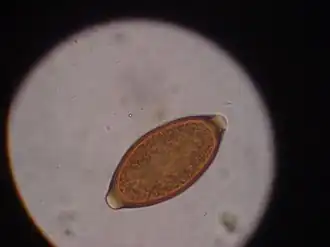

Trichuris

Trichuris est un genre de nématodes (les nématodes étant un embranchement de vers non segmentés, recouverts d'une épaisse cuticule et menant une vie libre ou parasitaire) de la famille des Trichuridae.

Les trichuris, parasites intestinaux, peuvent affecter les chiens mais rarement les chats en Amérique[2].